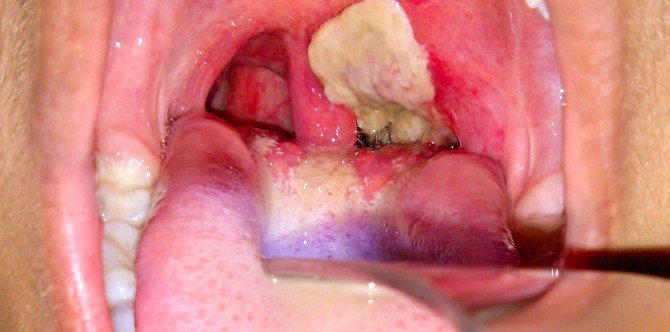

Sumber gambar: Laman FB Dr Zubaidi Hj Ahmad

Penyakit difteria kanak-kanak selalu menjangkiti tekak, iaitu bahagian tonsil, farinks, larinks dan hidung). Rupanya seperti lapisan selaput nanah berwarna kelabu-kehijauan pada saluran kerongkong pesakit sehingga jauh ke dalam saluran pernafasan atas.

- Lapisan selaput nanah berwarna kelabu-kehijauan pada saluran kerongkong